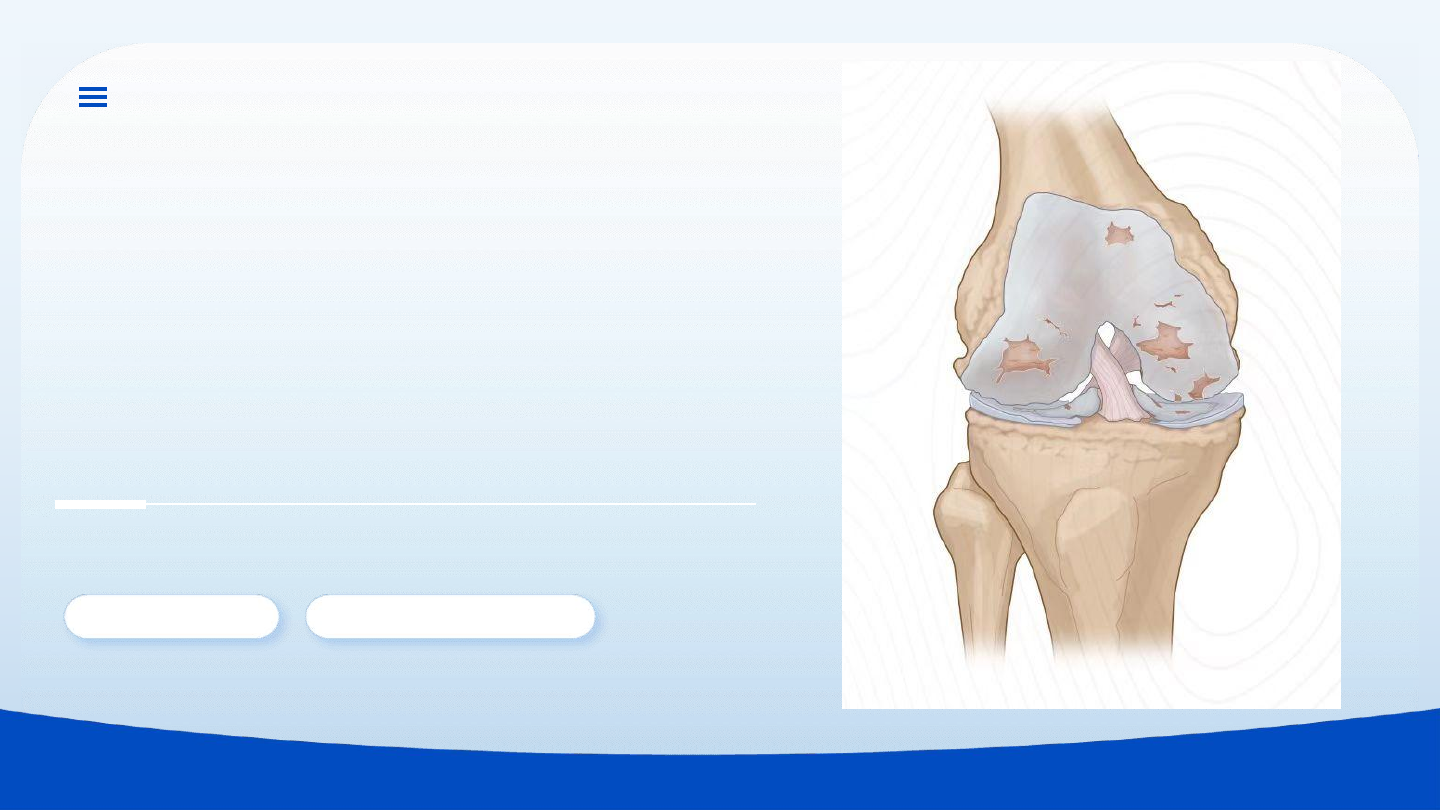

骨性关节炎并非简单的“骨刺病”,其本质是关节软骨的磨损

与丢失,是身体的“轴承”出了问题。

核心病变: 关节软骨退变、磨损、丢失。

继发改变: 机体为维稳,代偿性长出骨赘(骨刺)。

本质是软骨磨损,非骨刺病。